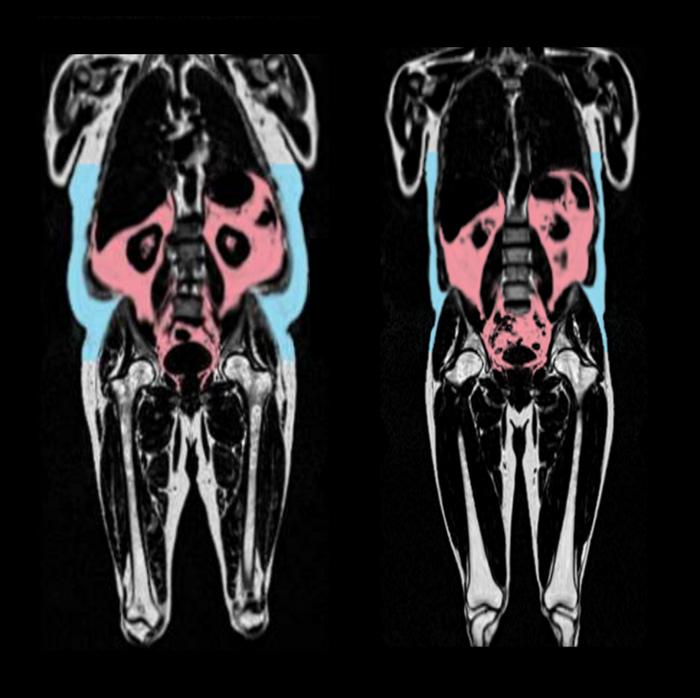

“Our research shows that ‘bad’ fat, hidden deep around the organs, accelerates aging of the heart. But some types of fat could protect against aging – specifically fat around the hips and thighs in women,” Declan O’Regan, a professor at Imperial College London, said in a statement.

The research also revealed a difference between men’s and women’s health. Fat around the belly was a marker of early heart aging in men, but it had the opposite effect in women. And there were ties between higher levels of the female hormone estrogen in premenopausal women and a slowdown of heart aging.

This analysis helped to uncover the link between heart aging and the fat, which cannot be seen externally and can exist in large quantities in people who are at a healthy weight.